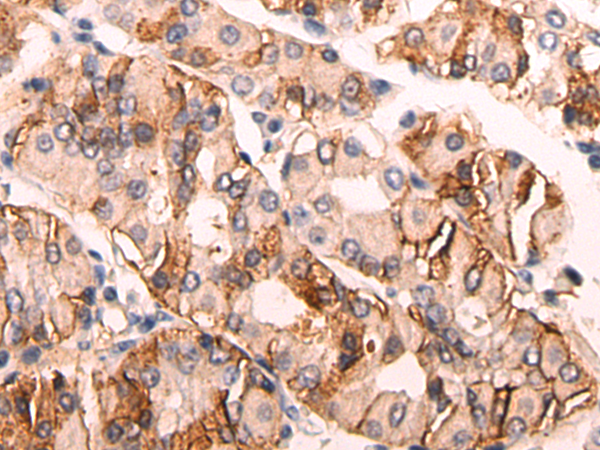

分类: 科研抗体货号: P12476别名: FIC; MARC; MCP3; NC28; MCP-3; SCYA6; SCYA7应用: IHC反应种属: Human

分类: 科研抗体货号: P12492别名: CR; CAL2; CAB29应用: WB,IHC反应种属: Human, Mouse, Rat

分类: 科研抗体货号: P12474别名:应用: WB,IHC反应种属: Human, Mouse, Rat

分类: 科研抗体货号: P12491别名: BARS应用: WB,IHC反应种属: Human, Mouse, Rat

分类: 科研抗体货号: P12503别名: CATL1; CPT1P; CPTIC; SPG73; CPT1-B; CPTI-B应用: IHC反应种属: Human, Mouse, Rat

分类: 科研抗体货号: P12490别名: CLP1; NSR2; SRCL; SCARA4应用: WB,IHC反应种属: Human, Mouse, Rat

分类: 科研抗体货号: P12502别名:应用: WB,IHC反应种属: Human

分类: 科研抗体货号: P12488别名: FB22; HM89; LAP3; LCR1; NPYR; WHIM; CD184; LAP-3; LESTR; NPY3R; NPYRL; WHIMS; HSY3RR; NPYY3R; D2S201E应用: IHC反应种属: Human, Mouse, Rat

分类: 科研抗体货号: P12501别名: SFTA5; SFTPJ应用: WB,IHC反应种属: Human